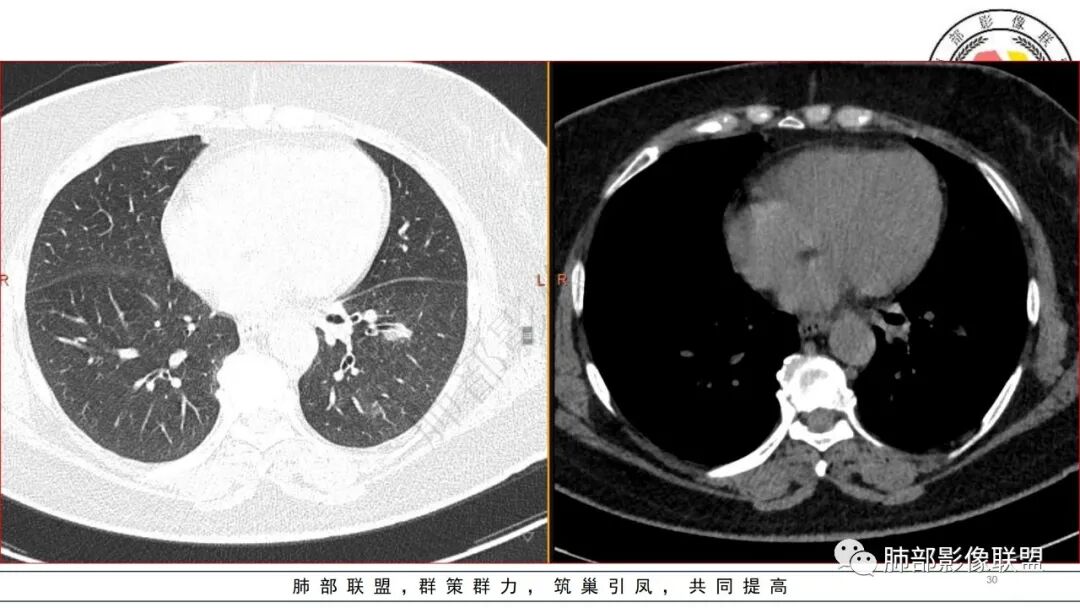

有糖尿病基层,左肺大片状实变影,跨多个叶段,多次治疗复查,实变范围有缩小,部分可见空洞影,考虑肺克

糖尿病,左下肺单侧实变,多次复查可见空洞和液平面,符合坏死性肺炎,白细胞高,遗憾的是不管是前期还是复查都没给PCT值,有手术史,首先考虑肺克,鉴别金葡和大肠埃希菌

糖尿病基础,左下肺感染性病变,进展快,先是左肺大片实变,短时间复查出现空洞,治疗两周周边有吸收好转,空洞壁变薄。金毛结克,我倾向金葡菌。鉴别肺克。

老年患者,糖尿病病史14年,不规律降糖治疗,血糖控制不佳,咳嗽、喘息两天就诊,查血常规白细胞轻度升高,CRP显著升高,首诊CT提示左下基底大片实变,边界不清,周围播散灶,短期复查病灶呈吸收好转趋势,并出现多发空洞,空洞形态不规则,病灶内未见气液平,考虑感染性病变:

2.左肺下叶大范围实性密度影,散乱,边界不清,可见液化空洞,病变肺体积轻度增大。支气管相关(相应支气管闭塞)。

3.五天后及十三天后病灶变化明显,实性密度影吸收缩小,边界趋于清楚,显示多空腔。

1.局限于单肺叶的大范围实性密度影,边界不清,看不出外壁的液化空洞,多符合化脓性感染。